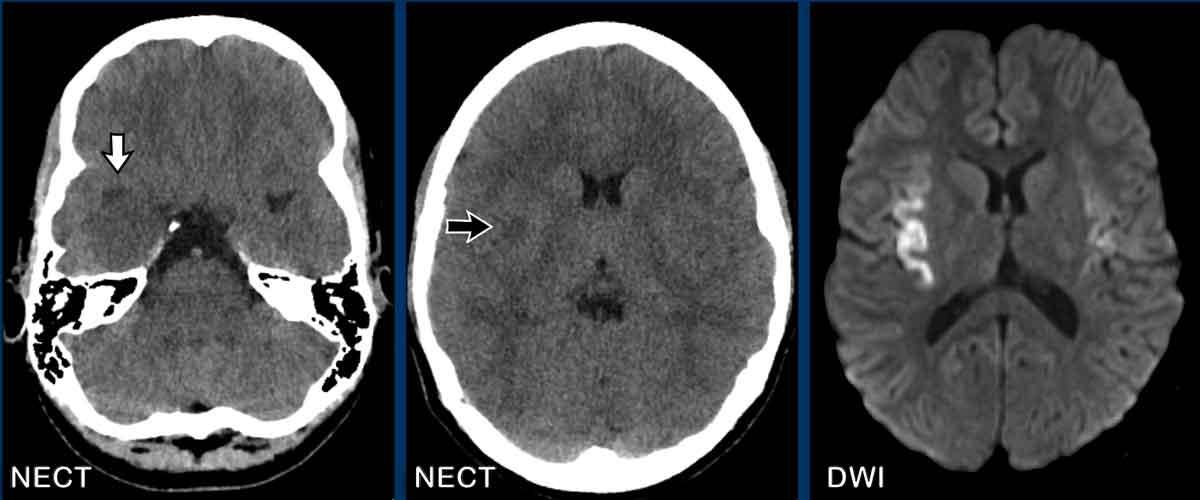

Viêm não Herpes

Một bệnh nhân nữ 13 tuổi nhập viện với triệu chứng đau đầu cấp tính và lú lẫn.

Hình ảnh

Chuỗi xung FLAIR cho thấy các vùng tăng tín hiệu lan rộng ở cả hai thùy thái dương và thùy đảo.

Tổn thương rõ hơn ở bên phải, nơi chuỗi xung T1W+Gd cho thấy ngấm thuốc dạng hồi não ở vỏ thùy đảo.

Đây là trường hợp điển hình của viêm não Herpes.

Tiếp tục xem thêm hình ảnh của bệnh nhân này…

Lưu ý các bất thường rất tinh tế trên CT không tiêm thuốc cản quang (NECT) so với các phát hiện trên MRI.

Thùy thái dương phải giảm tỷ trọng hơn so với bên trái, kèm theo hẹp nhẹ sừng thái dương phải (mũi tên trắng).

Cũng lưu ý vùng giảm tỷ trọng nhỏ ở dải vỏ thùy đảo (mũi tên đen).

CT kém nhạy hơn MRI và chỉ phát hiện được bất thường ở khoảng một nửa đến hai phần ba số bệnh nhân.

Có thể mất 3-4 ngày để các thay đổi ở thùy thái dương hoặc thùy trán mới biểu hiện rõ.

Các vùng giảm tỷ trọng, xuất huyết và phù não thường được ghi nhận, trong khi ngấm thuốc cản quang có thể mất gần một tuần mới xuất hiện.

Chuỗi xung DWI cho thấy hạn chế khuếch tán ở cả hai bên.

MRI nhạy hơn và có thể phát hiện các bất thường tinh tế như hạn chế khuếch tán ngay từ giai đoạn sớm.

Khi nghi ngờ chẩn đoán, cần chỉ định chọc dịch não tủy và bắt đầu điều trị kịp thời.